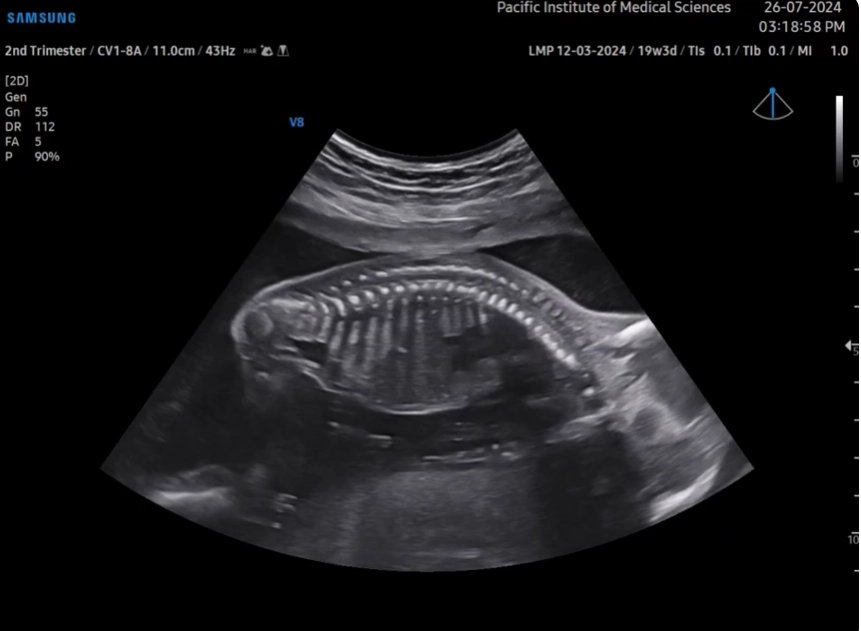

• Loạn sản xương không gây chết

Loạn sản sụn ở trẻ em (Achondroplasia)

• Loạn sản sụn ở trẻ em (Achondroplasia)